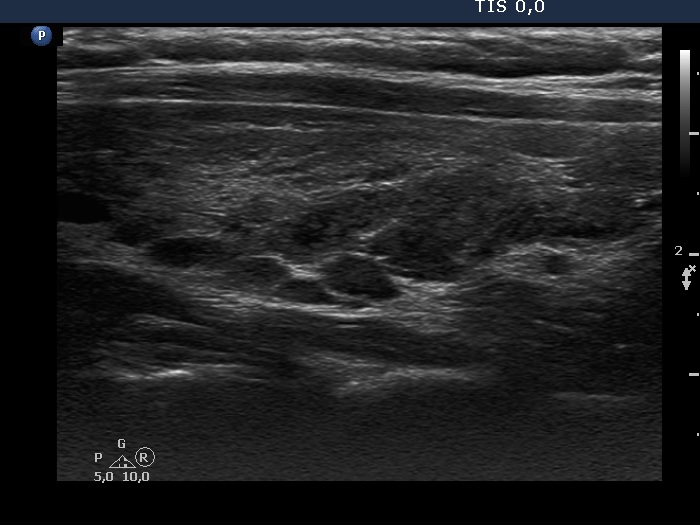

Consecutive patients with the final diagnosis of Hashimoto's thyroiditis - case 2 (23) (ultrasonographic picture 6)

Left lobe, longitudinal scan. The dorsal part of the lobe presents the so-called honey-combing pattern.